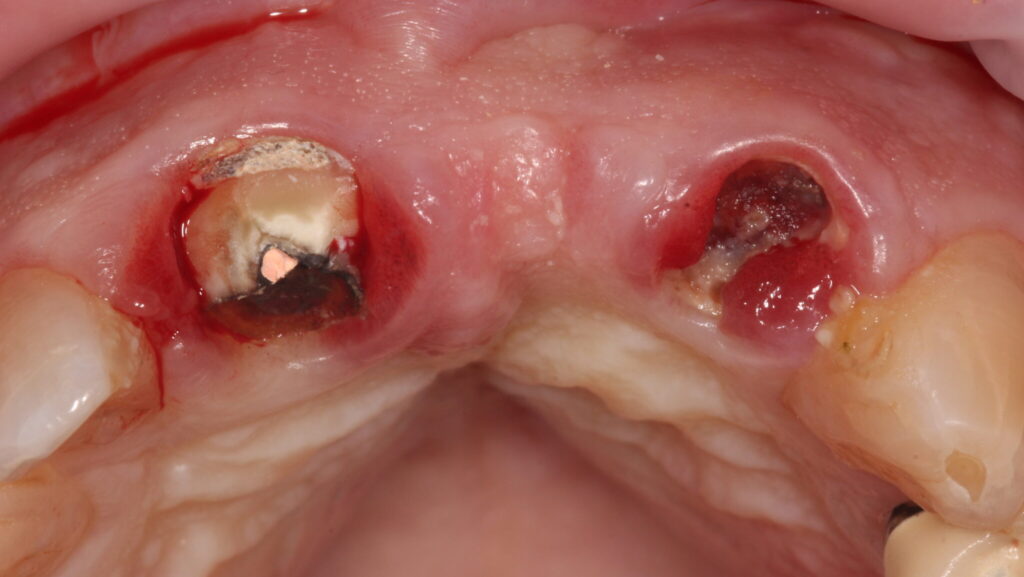

A 75-year-old male patient developed a problem with a tooth supported bridge for the upper right central and left central and lateral incisor teeth that had been in situ for more than twenty years. One of the supporting teeth had become loose and the referring dentist noticed the upper left abutment tooth was grossly carious and the three-unit bridge entirely supported by the upper right central incisor tooth.

Radiographic examination shows the upper left lateral incisor tooth has decayed through and through and the upper right central incisor tooth is heavily root treated and filled (Figs. 1-2).

The existing metal ceramic bridgework was thick and bulky, but the patient was used to it. The patient also didn’t have any pain or discomfort yet from the slightly loose bridge or dental caries. The patient was most concerned the bridge would suddenly come out and would have a space (Figs. 3-4).